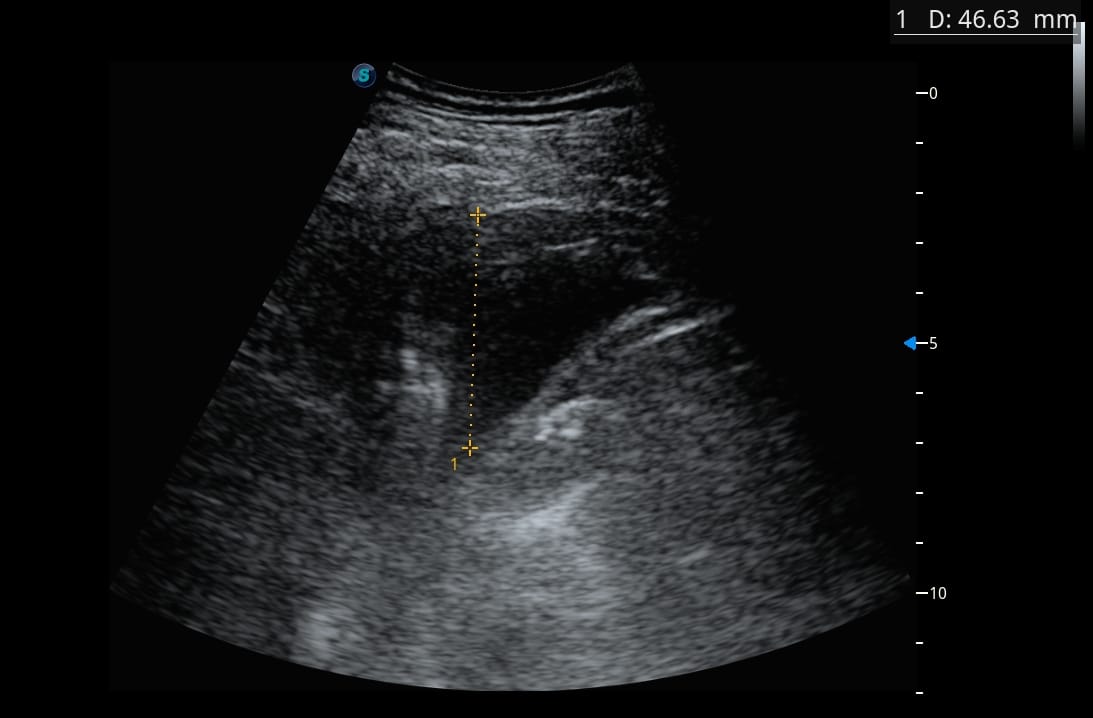

A gauche

Faites travailler votre œil et votre raisonnement avant la correction.

Quel est votre diagnostic ?

Analysez les images, repérez les éléments discriminants, puis confrontez votre hypothèse au raisonnement détaillé ci-dessous.

L’échographie pulmonaire va révéler des anomalies très marquées, en net décalage avec la clinique… avec des images particulièrement surprenantes du côté gauche.